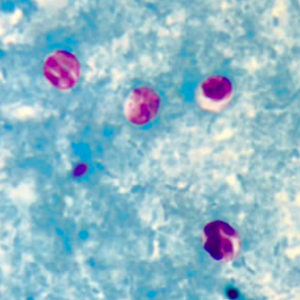

Les oocystes de cryptosporidie ne se colorent pas au Lugol. Ce sont des petites structures rondes mesurant entre 4 et 6 μm de diamètre, réfringentes. Leur contenu n’est pas visualisable en microscopie optique. Leur identification nécessite une coloration de Ziehl-Neelsen modifiée ; ils sont alors colorés en rose-rouge sur un fond bleu-vert. Il n’est pas possible de distinguer les différentes espèces sans technique de biologie moléculaire (Hoffman, 2017).